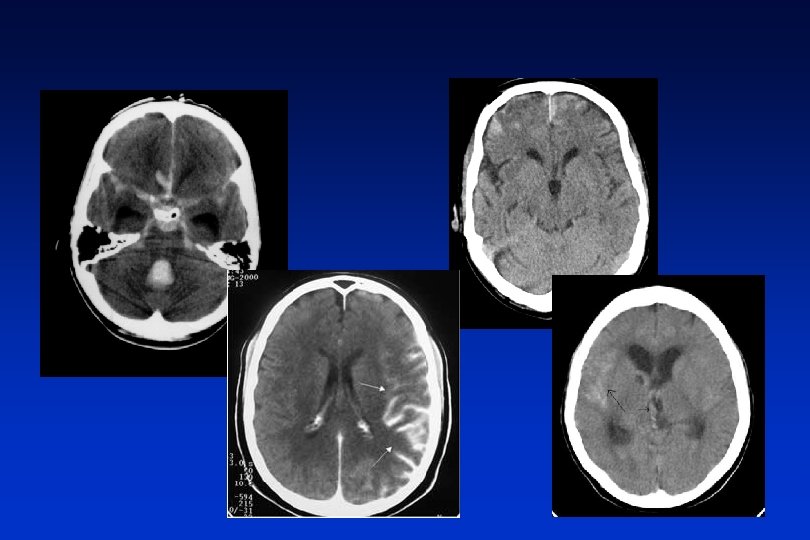

Hemorragia profunda - HTA Hemorragia lobar – otras causas

Causas y características hematomas intraparenquimatosos ETIOLOGIA Hipertensión arterial (40 -70%) LOCALIZACION* Ganglios de la base, cerebelo, tronco, sustancia blanca subcortical EDAD Mayores de 45 años Malformaciones vasculares (4 -10%) Lobares Jóvenes Angiopatía amiloidea (5 -10%) Lobares Ancianos Tumores cerebrales (2 -10%) Atípicas Anticoagulación, fibrinolisis (9 -14%) Lobares Drogas simpaticomiméticas Indeterminada (10%) Ancianos Jóvenes